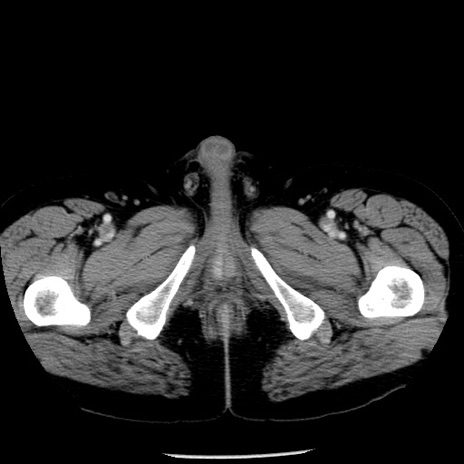

冠状断像

【症例】40歳代男性

【現病歴】2日前から胃痛あり。徐々に周期的な激痛に変化した。本日になっても激痛があるため受診。

【身体所見】意識清明、BT 38-39℃台あり、腹部:膨満、やや硬、右下腹部に圧痛あり。

【データ】WBC 8500、CRP 23.26